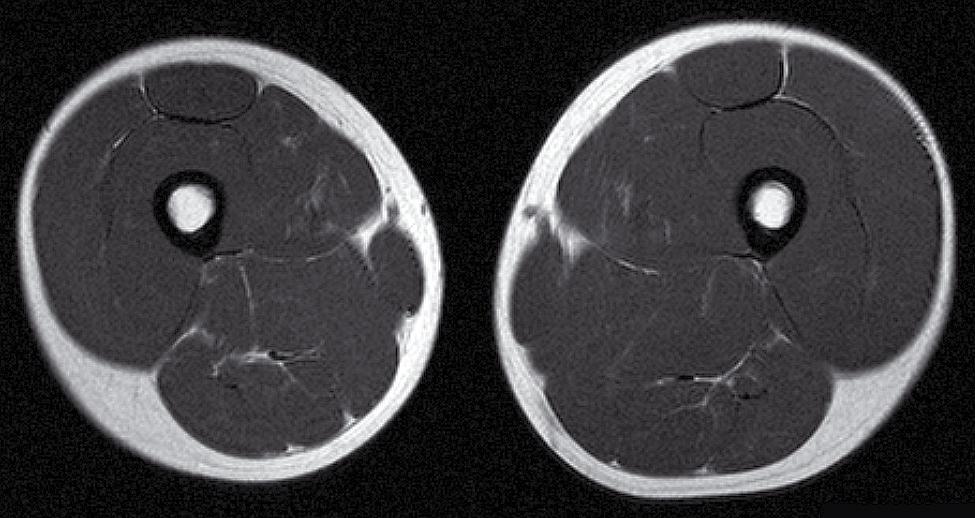

Bäckenhöjd, femuroch tibialängd liksom talus- och calcaneushöjd mäts på magnetkamerabilder.